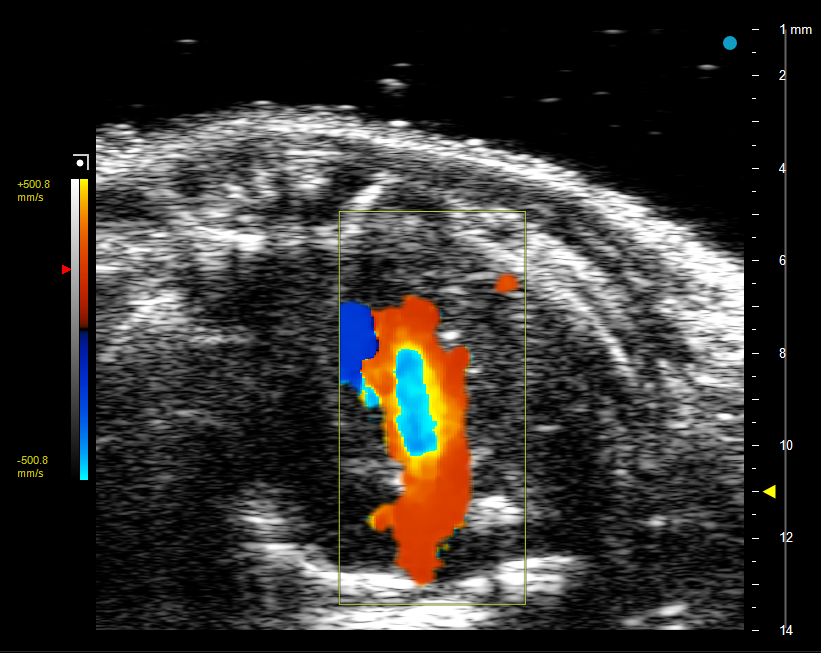

5.此时点击转换彩色多普勒(Color Doppler Flow Imaging,CDFI/CD)模式,取样框放置在左心室、左心房处,可以观察到红色、蓝色分别代表朝向、背离探头的血流,如图4所示,将脉冲波多普勒(Pulsed Wave Doppler, PW)取样容积放在左室血流速度最快的位置,点击转换成脉冲波多普勒模式,注意取样方向与血流方向一致,获取二尖瓣血流动力学信息,如图5所示,可以获取 E 峰、A 峰等定量参数。E 峰代表心室舒张早期被动充盈的血流速度,A 峰代表心房收缩主动充盈的血流速度,比值直接反映舒张期充盈模式。

图4 心尖四腔切面中二尖瓣血流信号显示

(Color Doppler Flow Imaging)